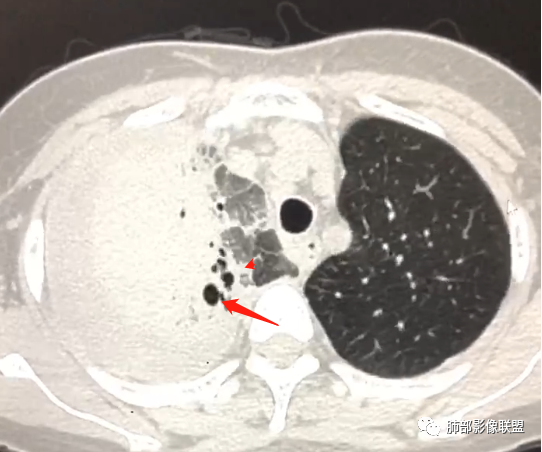

第二次CT:

10天后:胸水减少,右肺病变较前增大,内部未见坏死,含气支气管通畅。

下叶病变明显沿血管束分布

大叶性肺炎、无坏死空洞、间质为主,沿支气管血管束分布,伴随胸水。

单纯PPT的图像我考虑鹦鹉热。但是给的视频,明显支气管远端扩张。

问个问题:这是啥?空洞?扩张支气管?

感觉像是扩张的支气管,不确定

到底是不是坏死空洞?

这是扩张大支气管?还是囊腔?

空洞?

犹豫的点在于位置,与支气管关系。

一般空洞——应该在病灶的中央或实变区,这个在边缘。

囊腔?按理是近端支气管狭窄,导致气体潴留,不太符合。

因为大片实变支气管扩张原因:周围牵拉,支气管壁破坏。

这个在边缘,周围没有牵拉等因素,所以应该是壁的破坏。

壁破坏,这样的就需要观察整个壁的形态。